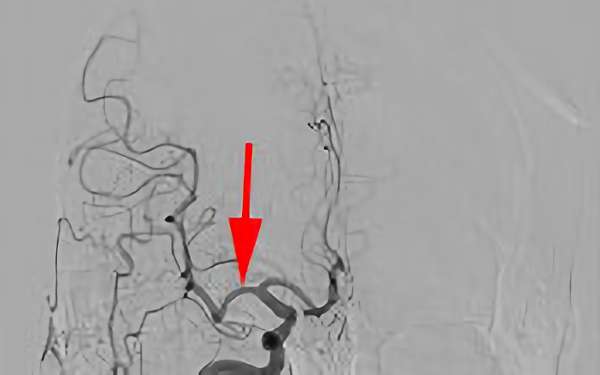

736

'20年1月15日

中大脳動脈塞栓症

80代

院内外来